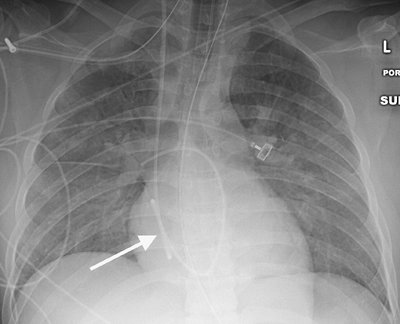

Coiling or redundancy of pulmonary artery catheter tubing in the right side of the heart can irritate the myocardial conduction bundle and result in dysrhythmias (Fig. 5-10). Other potential complications of pulmonary artery catheter placement

include pulmonary artery rupture (leading to pulmonary hemorrhage), pulmonary artery pseudoaneurysm (Figs. 5-11 and 5-12), fistulae between the pulmonary artery and the bronchial tree, intracardiac knotting of the catheter, and balloon rupture (Table 5-2). Complications that can occur with CVP catheter placement can also occur with pulmonary artery catheter placement (Fig. 5-13).

FIGURE 5-10. Looping of pulmonary artery catheter tubing. AP chest radiograph shows looping of the pulmonary artery catheter tubing (arrow) over the expected right atrium. This redundancy of catheter tubing can lead to dysrhythmias.